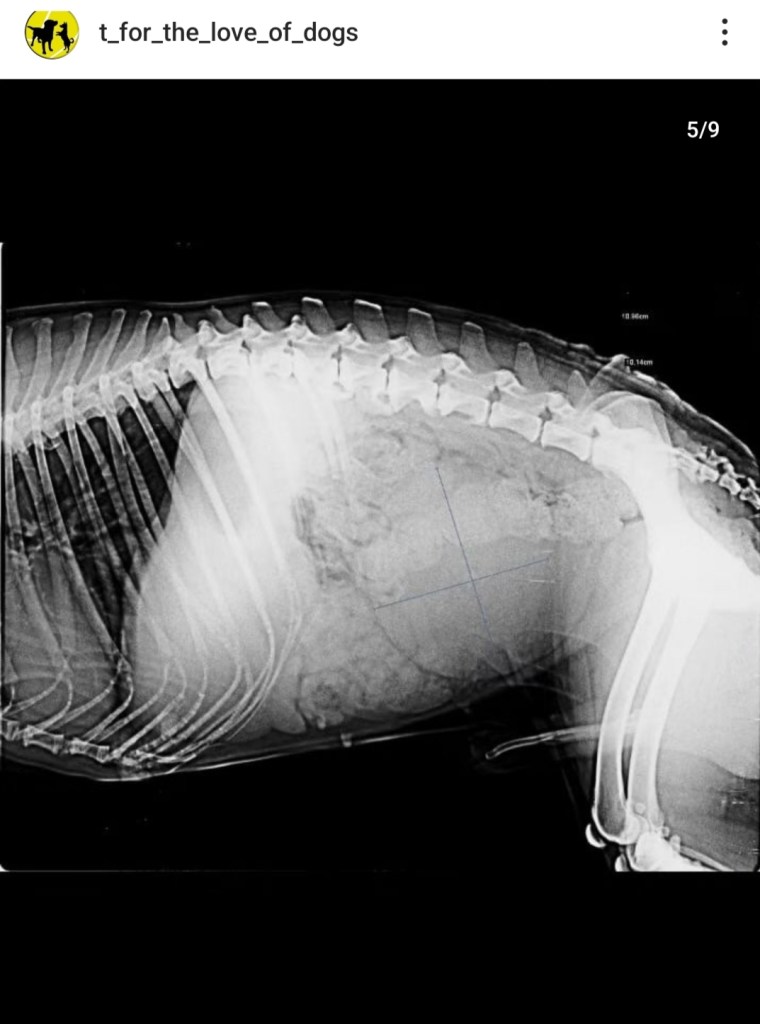

This is Lalu.

After investigation it is found that he has a tumor in his bladder almost as big as his bladder.